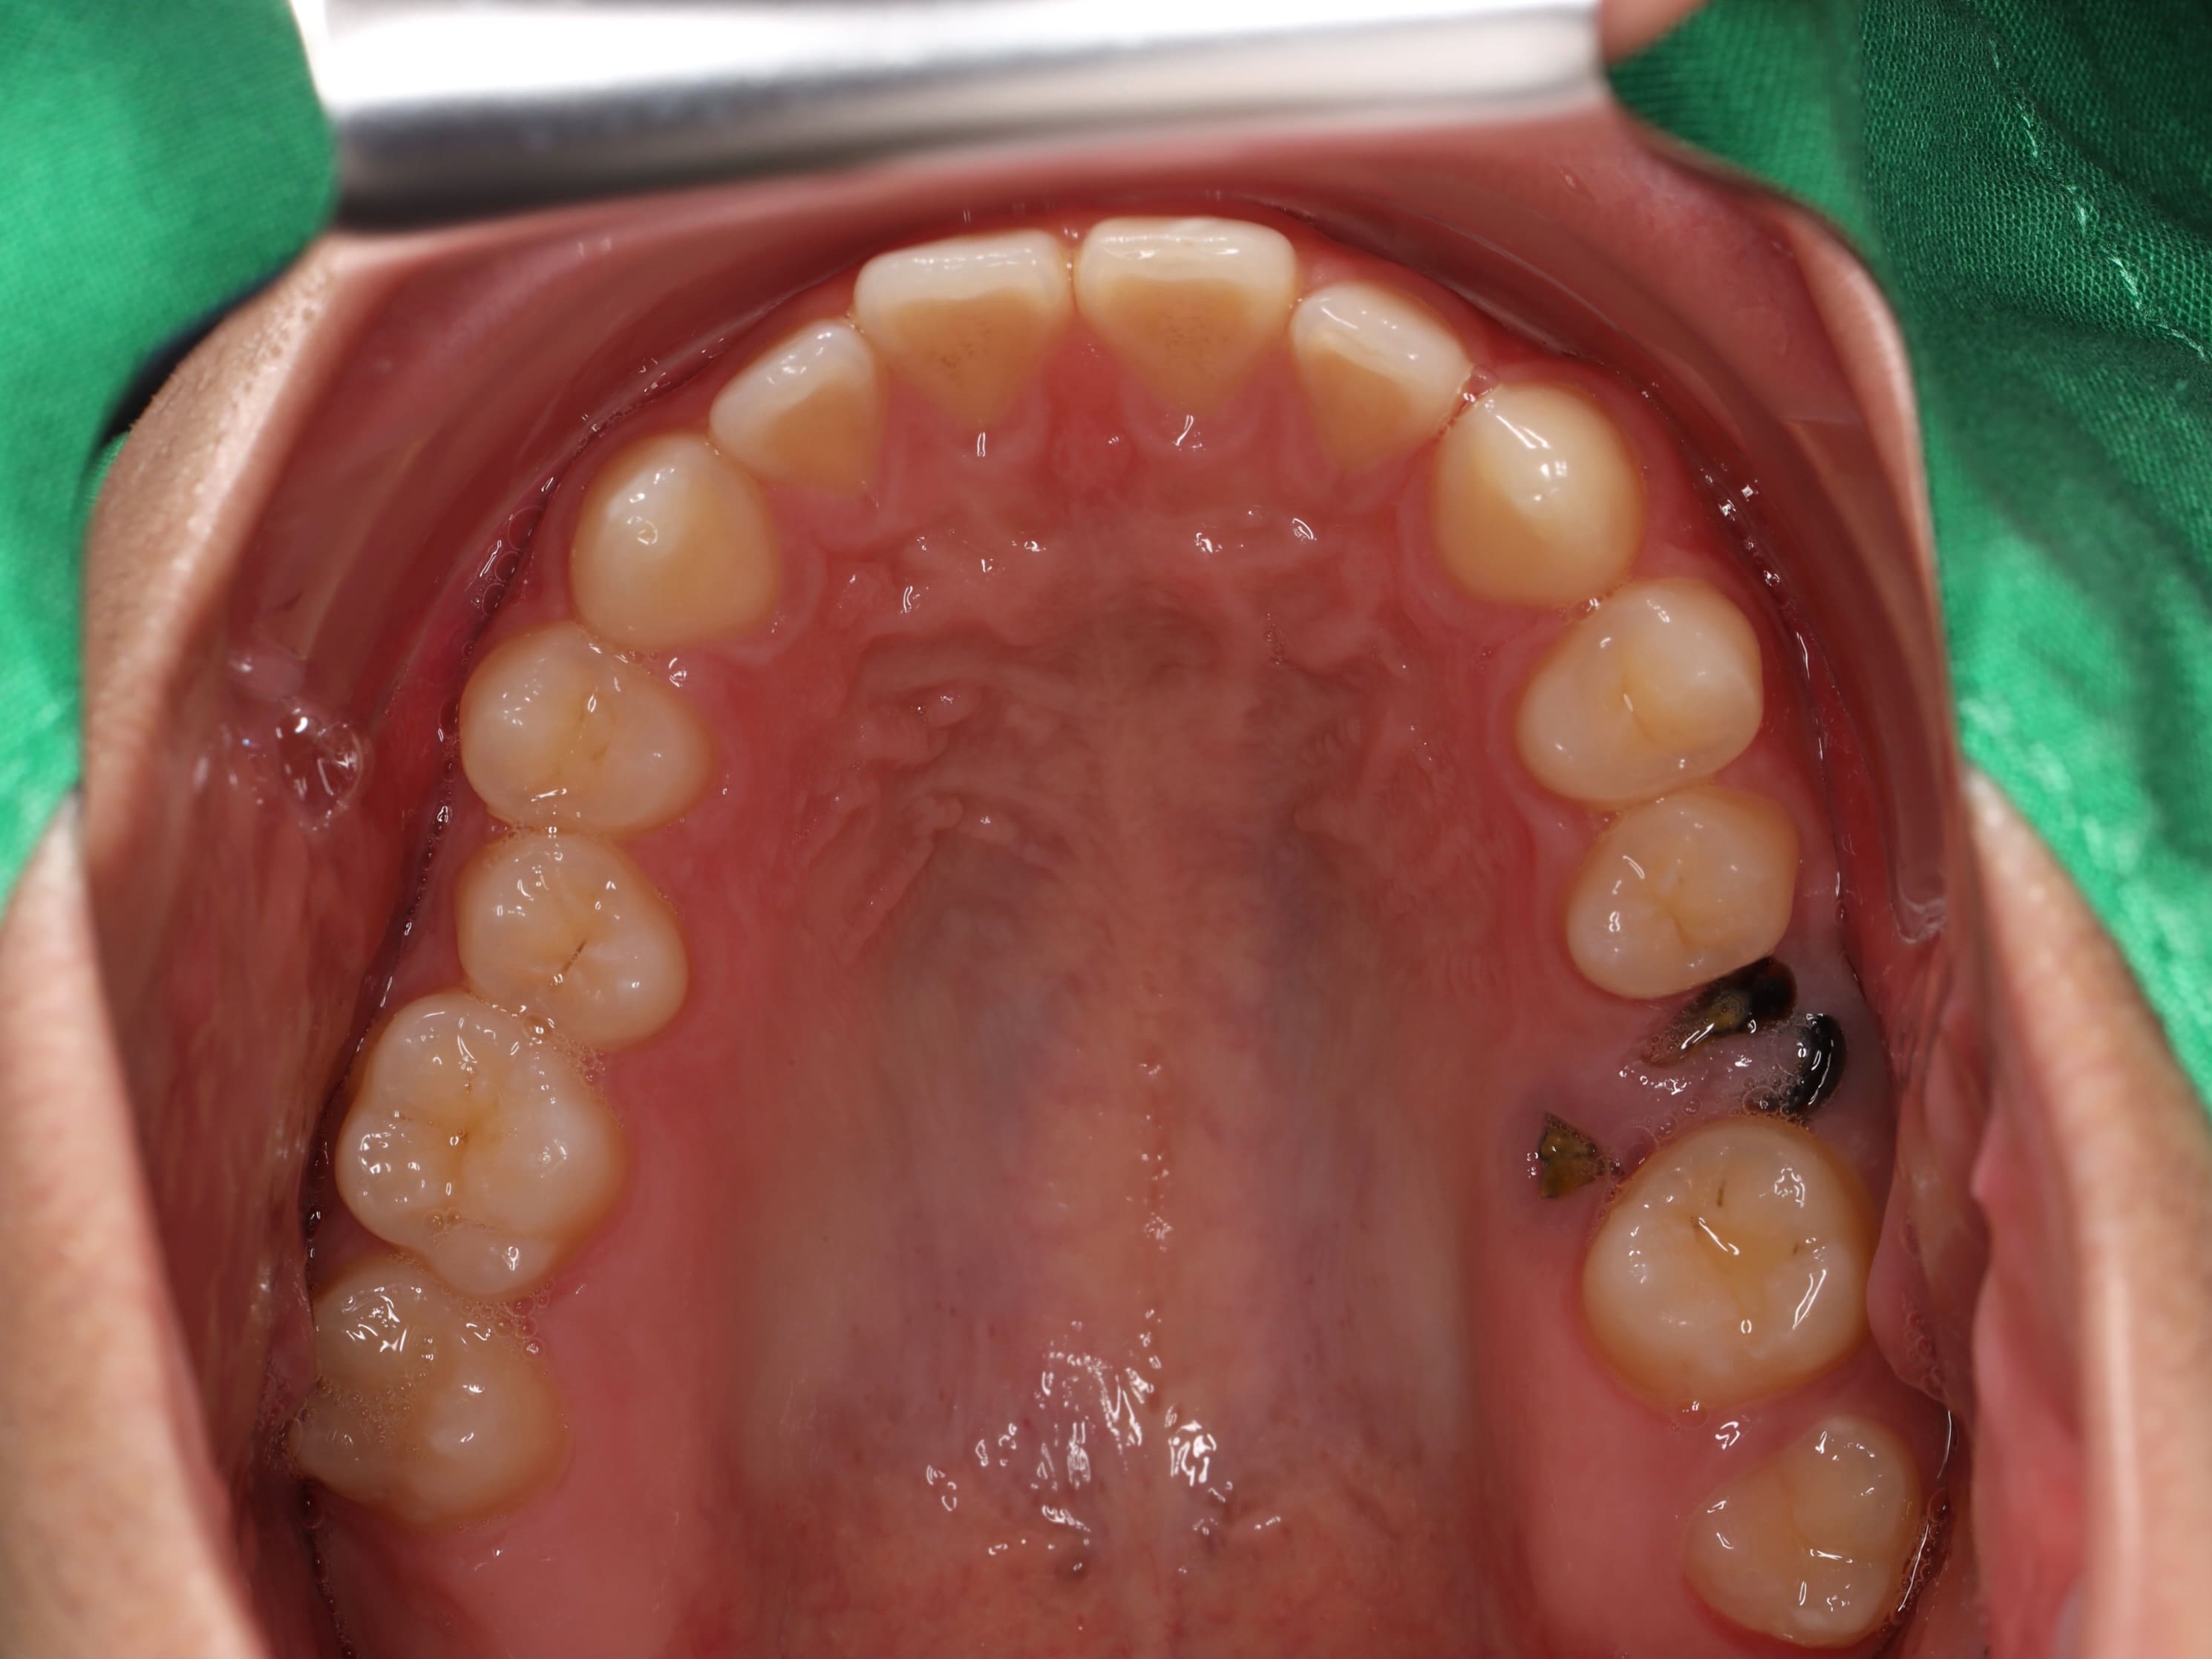

經過仔細檢查後,我們發現病患的口腔狀況存在幾個需要處理的問題。首先是左上方的臼齒因為嚴重蛀牙只剩下牙根,導致兩側的牙齒失去支撐而逐漸傾倒,進而影響了整體的牙齒排列。另外,下排牙齒有錯咬的狀況,造成下巴看起來往前凸。除此之外,由於病患本身的牙齒比例偏短,笑的時候牙齦露出的面積相對比較多,影響了整體的美觀性。

針對這些問題,我們擬定了完整的治療方案。首先,利用矯正的方式,將後方的第二大臼齒和智齒慢慢往前移動,填補缺牙的空間,同時調整上下排牙齒的咬合關係,讓錯咬的情況回復到正常的咬合狀態。當矯正治療完成後,病患的狀況其實已經改善了許多。